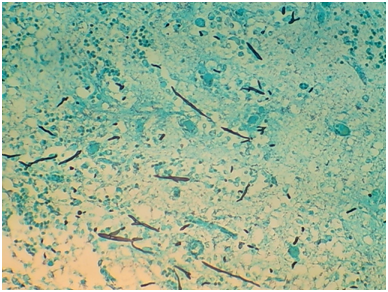

Autopsy of the decedent demonstrated disseminated invasive aspergillosis with multiple cavitating, necrotic, hemorrhagic, friable, soft, red and yellow-white lesions in both lungs (Figure 1), severe pericardial and pleural adhesions of the lungs, and hemorrhagic and cavitating soft masses in cerebrum (Figure 2) and cerebellum. Histologic examination of lungs revealed necrotizing pneumonia with sharply delineated rounded foci with hemorrhagic borders. Alveoli are filled with neutrophilic exudates with breakdown of the alveolar septa and formation of abscesses (Figure 3). In the brain there were multiple cavitating, hemorrhagic, friable, necrotic, soft yellow lesions. Microscopic sections demonstrated red blood cells and inflammatory cells in the involved area (Figure 4). GMS staining showed septate hyphae that branched dichotomously at acute angles, consistent with Aspergillus fungus (Figures 5&6). The fungal colonies were confined to the necrotic material and appeared as branching, slender, septate hyphae (Figures 5&6). There was no evidence of infection of the heart, pancreas, kidneys, liver, spleen, or adrenal glands.